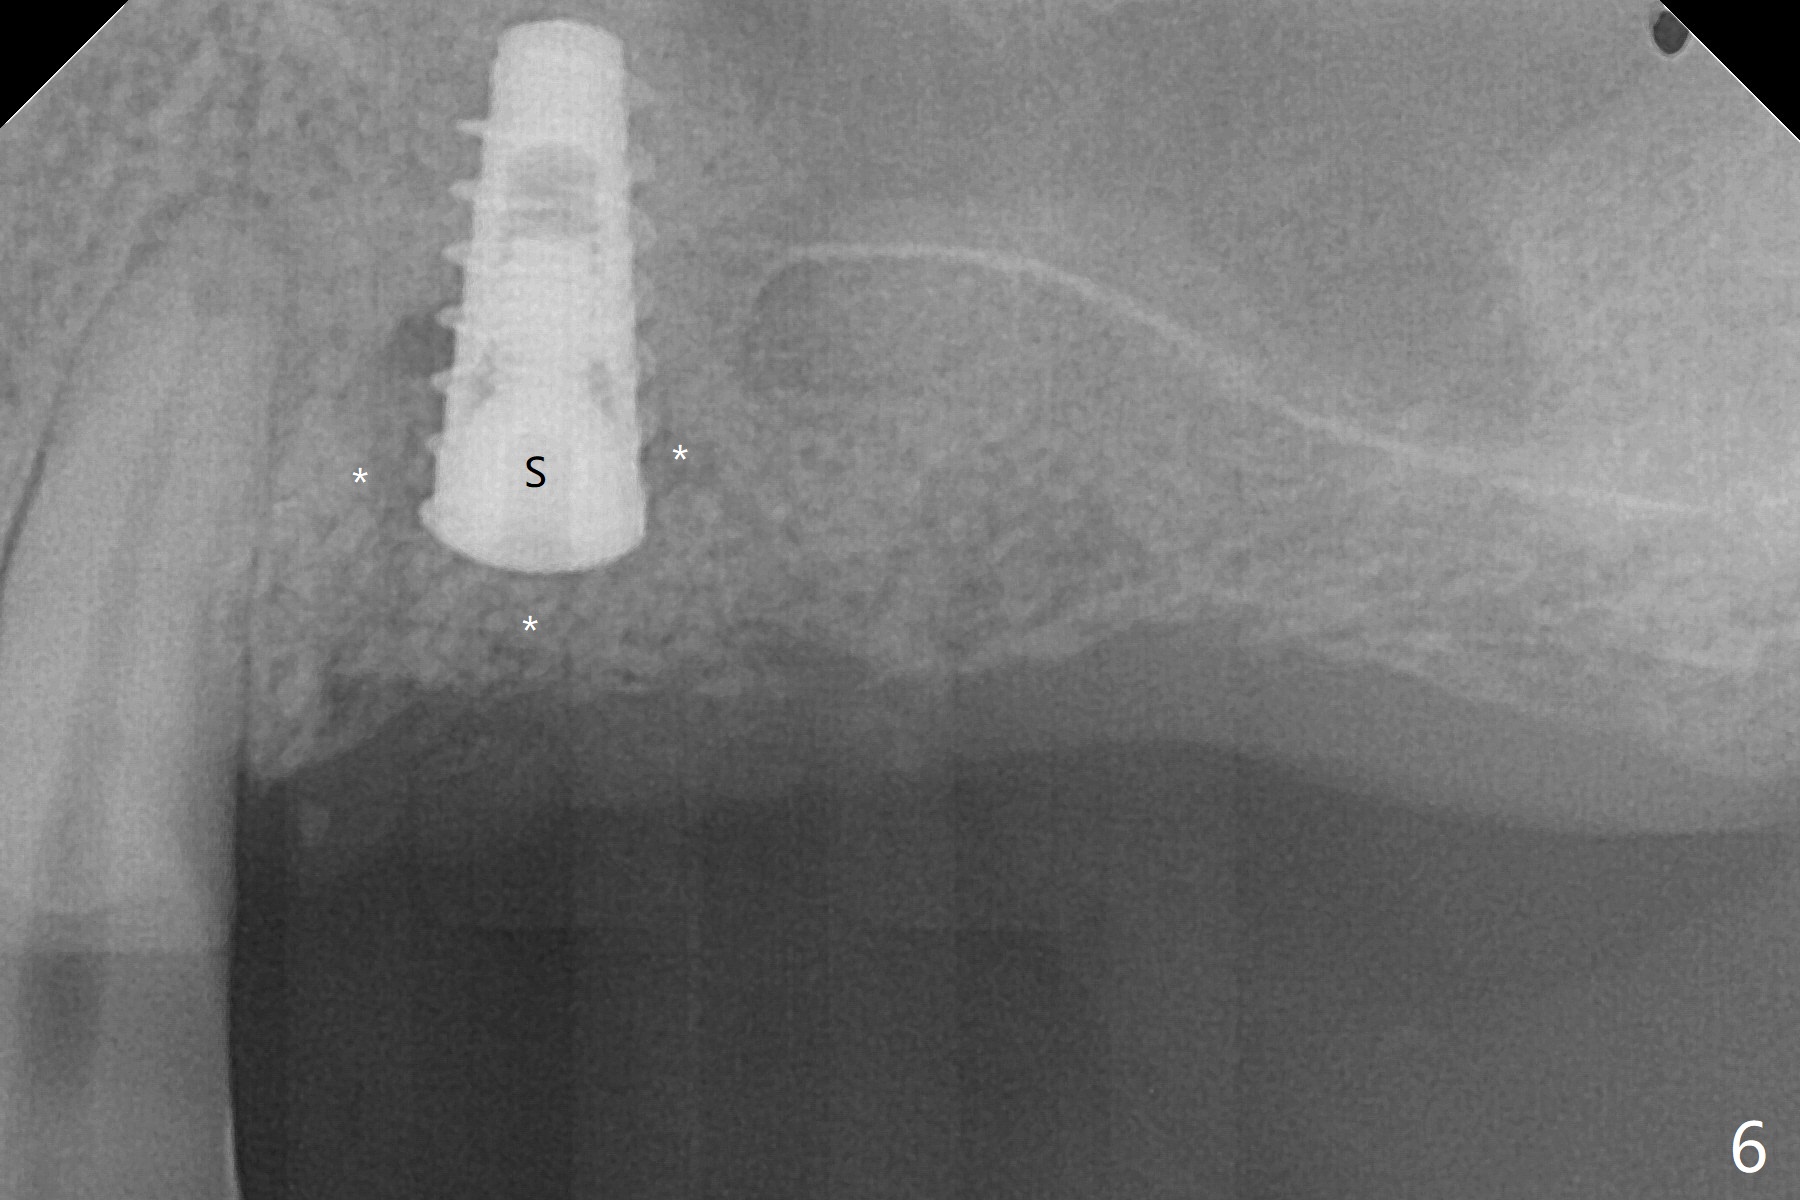

Five months post implant removal and bone graft, incision is made at #12. Osteotomy is being done with guide until 3.0x7.3 mm drill with 1 O-ring (palatal wall being thin), followed by 3.2x17-19 mm sinus round drills and 2.2x11.5 mm drill. After placement of 2 small loads of bone graft, a 4x9 mm dummy implant is inserted for sinus lift (Fig.1,2 *). By this time, the buccal plate is gone, while there is apparently the palatal periosteum. With more bone graft for sinus lift, a 4x9 mm final implant is placed with 30 Ncm (machine) and 4 mm subgingival (Fig.3,4 double arrows). Sticky bone (Fig.5,6 *) is applied around the coronal end of the implant and cover screw (S), followed by 2 pieces of PRF and 4-0 PGA suture. The sutures appear to have been dissolved and PRF membrane exposed 7 days postop (Fig.7,8 (smoker)). Four months postop, the wound heals except a small hole, which seems to be communicated with the underlying implant (Fig.9). The sinus lift remains (Fig.10 <), while bone loss appears to be present around the implant (Fig10,11 *). After placement of 5.5x4 mm healing abutment and before suturing, allograft is pushed into periimplant space (Fig.12, 13 *).